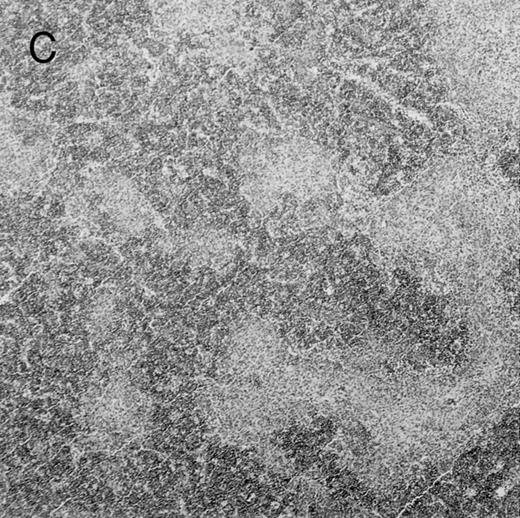

Histologic findings. Organs were collected at different times after BMT and tissue sections were stained with hematoxylin and eosin. Original magnifications for spleen (left) and liver (right) are ×40 and ×100, respectively. (A) B6 mice receiving FVB BM plus EpTK T cells. (B) Control group receiving BM only.

(C) B6 mice receiving FVB BM plus EpΔTK T cells and treated with GCV. (D) B6 mice receiving FVB BM plus EpΔTK T cells, treated with GCV, and developing a late onset GVHD (day 54).

FVB BM-grafted B6 mice: a model of lethal GVHD.We developed a model of GVHD resulting in 100% mortality soon after BMT using FVB mice, a strain not previously used as BM donors in experimental allogeneic BMT. We tested different combinations of recipient irradiation doses, as well as injected BM cell and CD3+ peripheral T-cell numbers. When 10-Gy–irradiated B6 mice were reconstituted with 107 FVB BM cells, we observed prolonged survival, whereas all ungrafted animals died before day 16 (Fig 2). In these conditions, more than 98% of splenocytes were of donor origin (Fig 3A). When 107 CD3+ peripheral T cells from mice of FVB genetic background were added to the FVB BMT, all animals died of GVHD between days 7 and 34 (Fig 2). Similar results were obtained using either PBS-treated mice receiving EpTK or EpΔTK peripheral T cells or GCV-treated mice receiving FVB nontransgenic peripheral T cells. Notably, this observation also indicates that both TK- and ΔTK-expressing T cells in the absence of GCV are fully competent to induce a lethal GVHD. Histopathologic examination of spleen and liver of these animals showed characteristic GVHD lesions such as (1) architecture disruption, necrosis, and congestion in the spleen; (2) hepatic periportal necrosis; (3) mononuclear portal infiltrates; and (4) endothelialitis of portal or centrolobular veinules (Fig 4A). By comparison, B6 mice receiving only FVB BM had a normal histology (Fig 4B).

Protection from GVHD was slightly less efficient in the group receiving EpΔTK CD3+ T cells. The survival rate was 79% at day 60 and 67% at day 120 (Fig 2B). However, two different outcomes must be distinguished. On the one hand, a majority of mice behaved as GCV-treated animals receiving EpTK T cells. They were apparently healthy, presented no skin lesions during a 120-day observation period, and showed complete donor-type hematologic reconstitution. There were no histological signs of GVHD in the spleen or liver (Fig 4C).